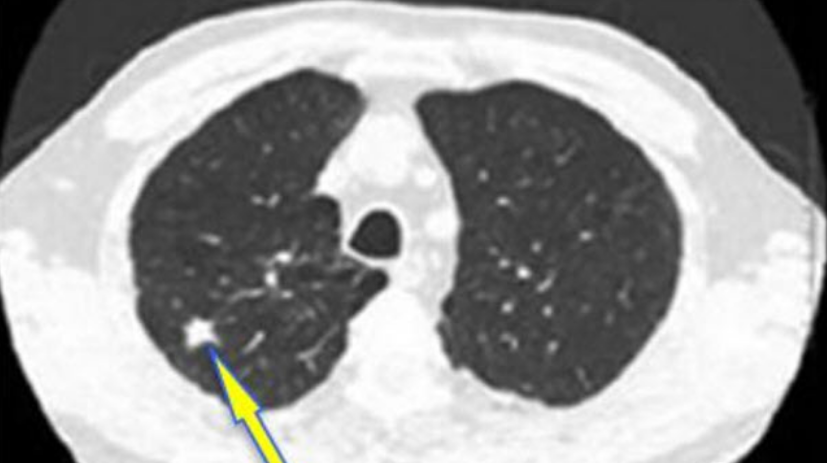

肺结节是指肺脏的组织内出现的病变,CT上是直径≤30mm的局灶性、类圆形、密度增高的实性或亚实性肺部阴影。肺结节就像是肺上长了个“小坨”或“小疤”,是一种客观的影像描述,并不是一种疾病的诊断,更不能代表就是肺癌。

● 根据结节的密度,可以分为:

实性结节

类似单独分离的鸡蛋黄。

纯磨玻璃结节

类似鸡蛋清,隐约可见其中的结构。

部分实性结节

也叫混合磨玻璃结节。它的结构如同一个荷包蛋,磨玻璃成分类似其中的蛋清,而实性且密度较高的部分则类似蛋黄。

● 恶性结节

普遍长得比较嚣张且颜值低:有分叶、毛刺,分界不清,供血丰富。

这种结节看起来就像个刺头,一点都不老实,模糊分界是因为想往正常肺组织里扩张捣乱又不想太高调,丰富的供血可以悄咪咪地吸收周围组织营养让自己迅速生长。